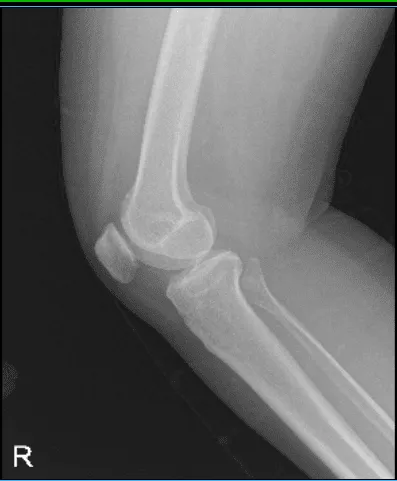

X-ray result showed Mild osteoarthrosis in the medial and anterior compartment of the knee